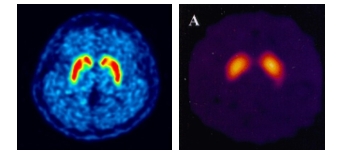

피디뷰는 퓨쳐켐의 플루오린(F-18) 표지 기술을 통해 세계 최초로 상용화한 파킨슨병 진단 신약이다.

뇌 속 도파민 운반체의 농도를 정량적으로 분석해 파킨슨병을 진단하는 원리다. 미국에선 피디뷰와 화합물이 같은 G사의 경쟁약물이 FDA 승인을 받은 상황이어서 피디뷰의 505(b)2의 승인 가능성이 높이 점쳐지고 있다.

특히 미국은 현재 요오드(I-123) 표지 의약품이 널리 사용되고 있는데, 피디뷰는 해당 의약품 대비 가격경쟁력이 높고 빠르게 영상을 취득할 수 있다. 또 경쟁사의 SPECT-CT 방식 대신 PET-CT 방식을 채택해 영상 퀄리티가 높은 것도 장점이라고 회사는 설명했다.